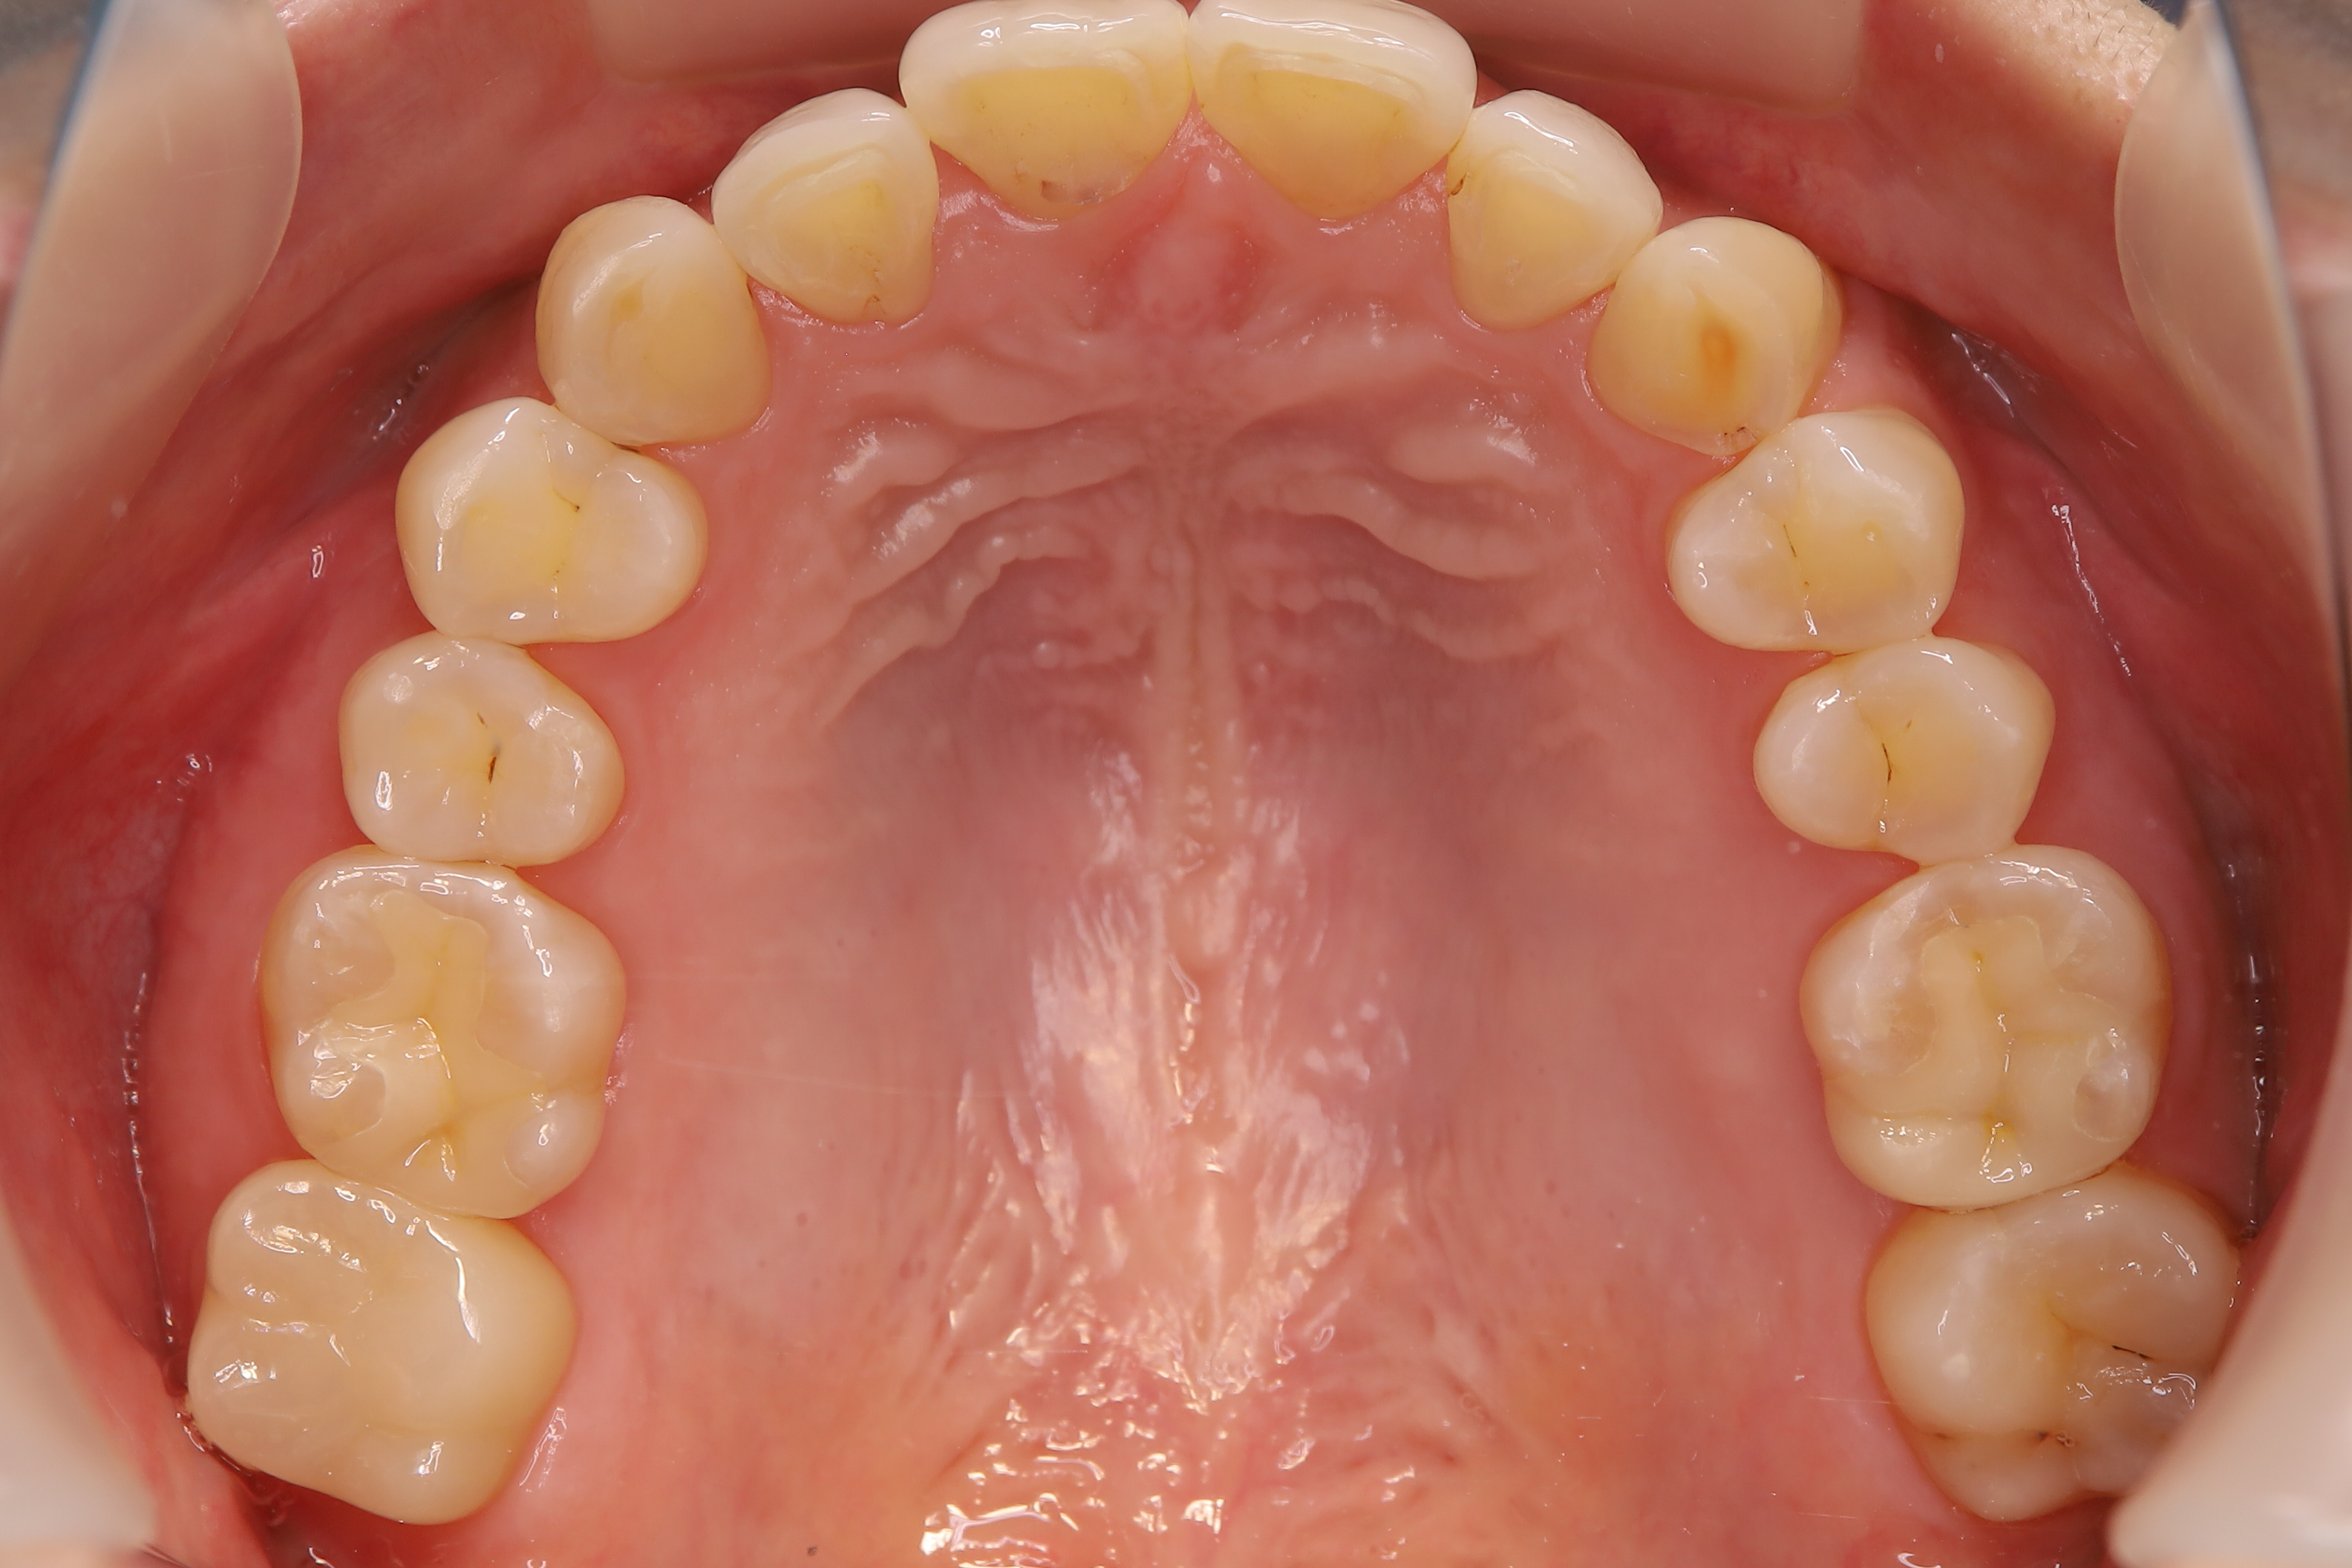

審美歯科治療

症例紹介